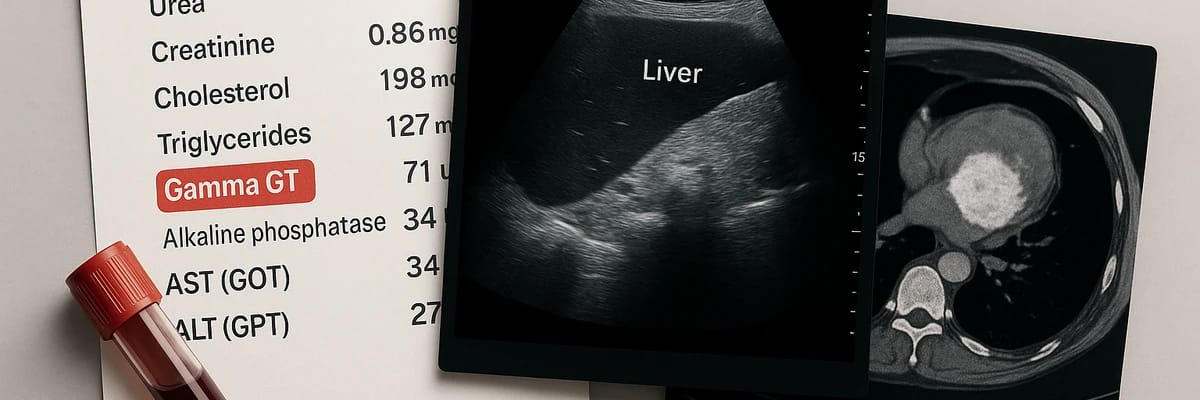

Examens d’imagerie pour explorer le foie

Après les bilans sanguins, l’étape suivante consiste à visualiser le foie. Les chiffres ne suffisent pas toujours. Les examens d’imagerie permettent de vérifier l’aspect du foie, d’identifier une éventuelle surcharge graisseuse, une obstruction biliaire ou même une tumeur.

Transition : Chaque technique d’imagerie a ses avantages, ses indications, et ses limites. Voici un panorama détaillé des examens les plus utilisés.

1. L’échographie abdominale

L’échographie est l’examen de première intention. Elle est simple, indolore, peu coûteuse et largement disponible. Elle utilise des ultrasons pour produire des images en temps réel du foie, de la vésicule biliaire et des voies biliaires.

Pourquoi est-elle si utile ?

- Elle détecte la stéatose hépatique (foie gras).

- Elle identifie des signes de cirrhose (foie irrégulier, nodulaire).

- Elle visualise une obstruction biliaire (calcul, dilatation des voies).

Ses limites : elle ne permet pas de détecter toutes les lésions, surtout si elles sont petites ou situées dans des zones difficiles d’accès.

2. Le scanner (CT-scan) abdominal

Le scanner est souvent demandé en deuxième intention, si l’échographie révèle une anomalie suspecte. Il utilise des rayons X pour obtenir des images précises en coupe du foie et de l’abdomen.

Ses atouts : - Très précis pour visualiser la taille du foie et sa texture.

- Permet de détecter tumeurs, métastases et anomalies vasculaires.

- Évalue aussi les autres organes voisins (pancréas, reins).

Ses inconvénients : l’irradiation aux rayons X et l’injection de produit de contraste iodé, parfois contre-indiquée (allergie, insuffisance rénale).

3. L’IRM hépatique

L’IRM est l’examen le plus précis pour explorer le foie. Elle utilise un champ magnétique et des ondes radio, sans irradiation.

Ses principaux avantages :

- Elle détecte très finement les lésions (tumeurs, fibroses, anomalies biliaires).

- Elle différencie les types de lésions (ex. bénignes vs malignes).

- Elle offre une cartographie détaillée des tissus hépatiques.

Ses limites : durée de l’examen (long, parfois inconfortable), coût plus élevé, contre-indications (pacemaker, implants métalliques).

4. La Fibroscan®

Le Fibroscan® est un examen plus récent et de plus en plus utilisé. Il ressemble à une échographie mais mesure la rigidité du foie.

Pourquoi est-ce intéressant ? Parce qu’un foie rigide indique une fibrose, voire une cirrhose. Cela permet d’éviter une biopsie dans certains cas.

Cet examen est rapide, indolore, non invasif. Mais il reste un outil de dépistage, à compléter par d’autres examens si nécessaire.